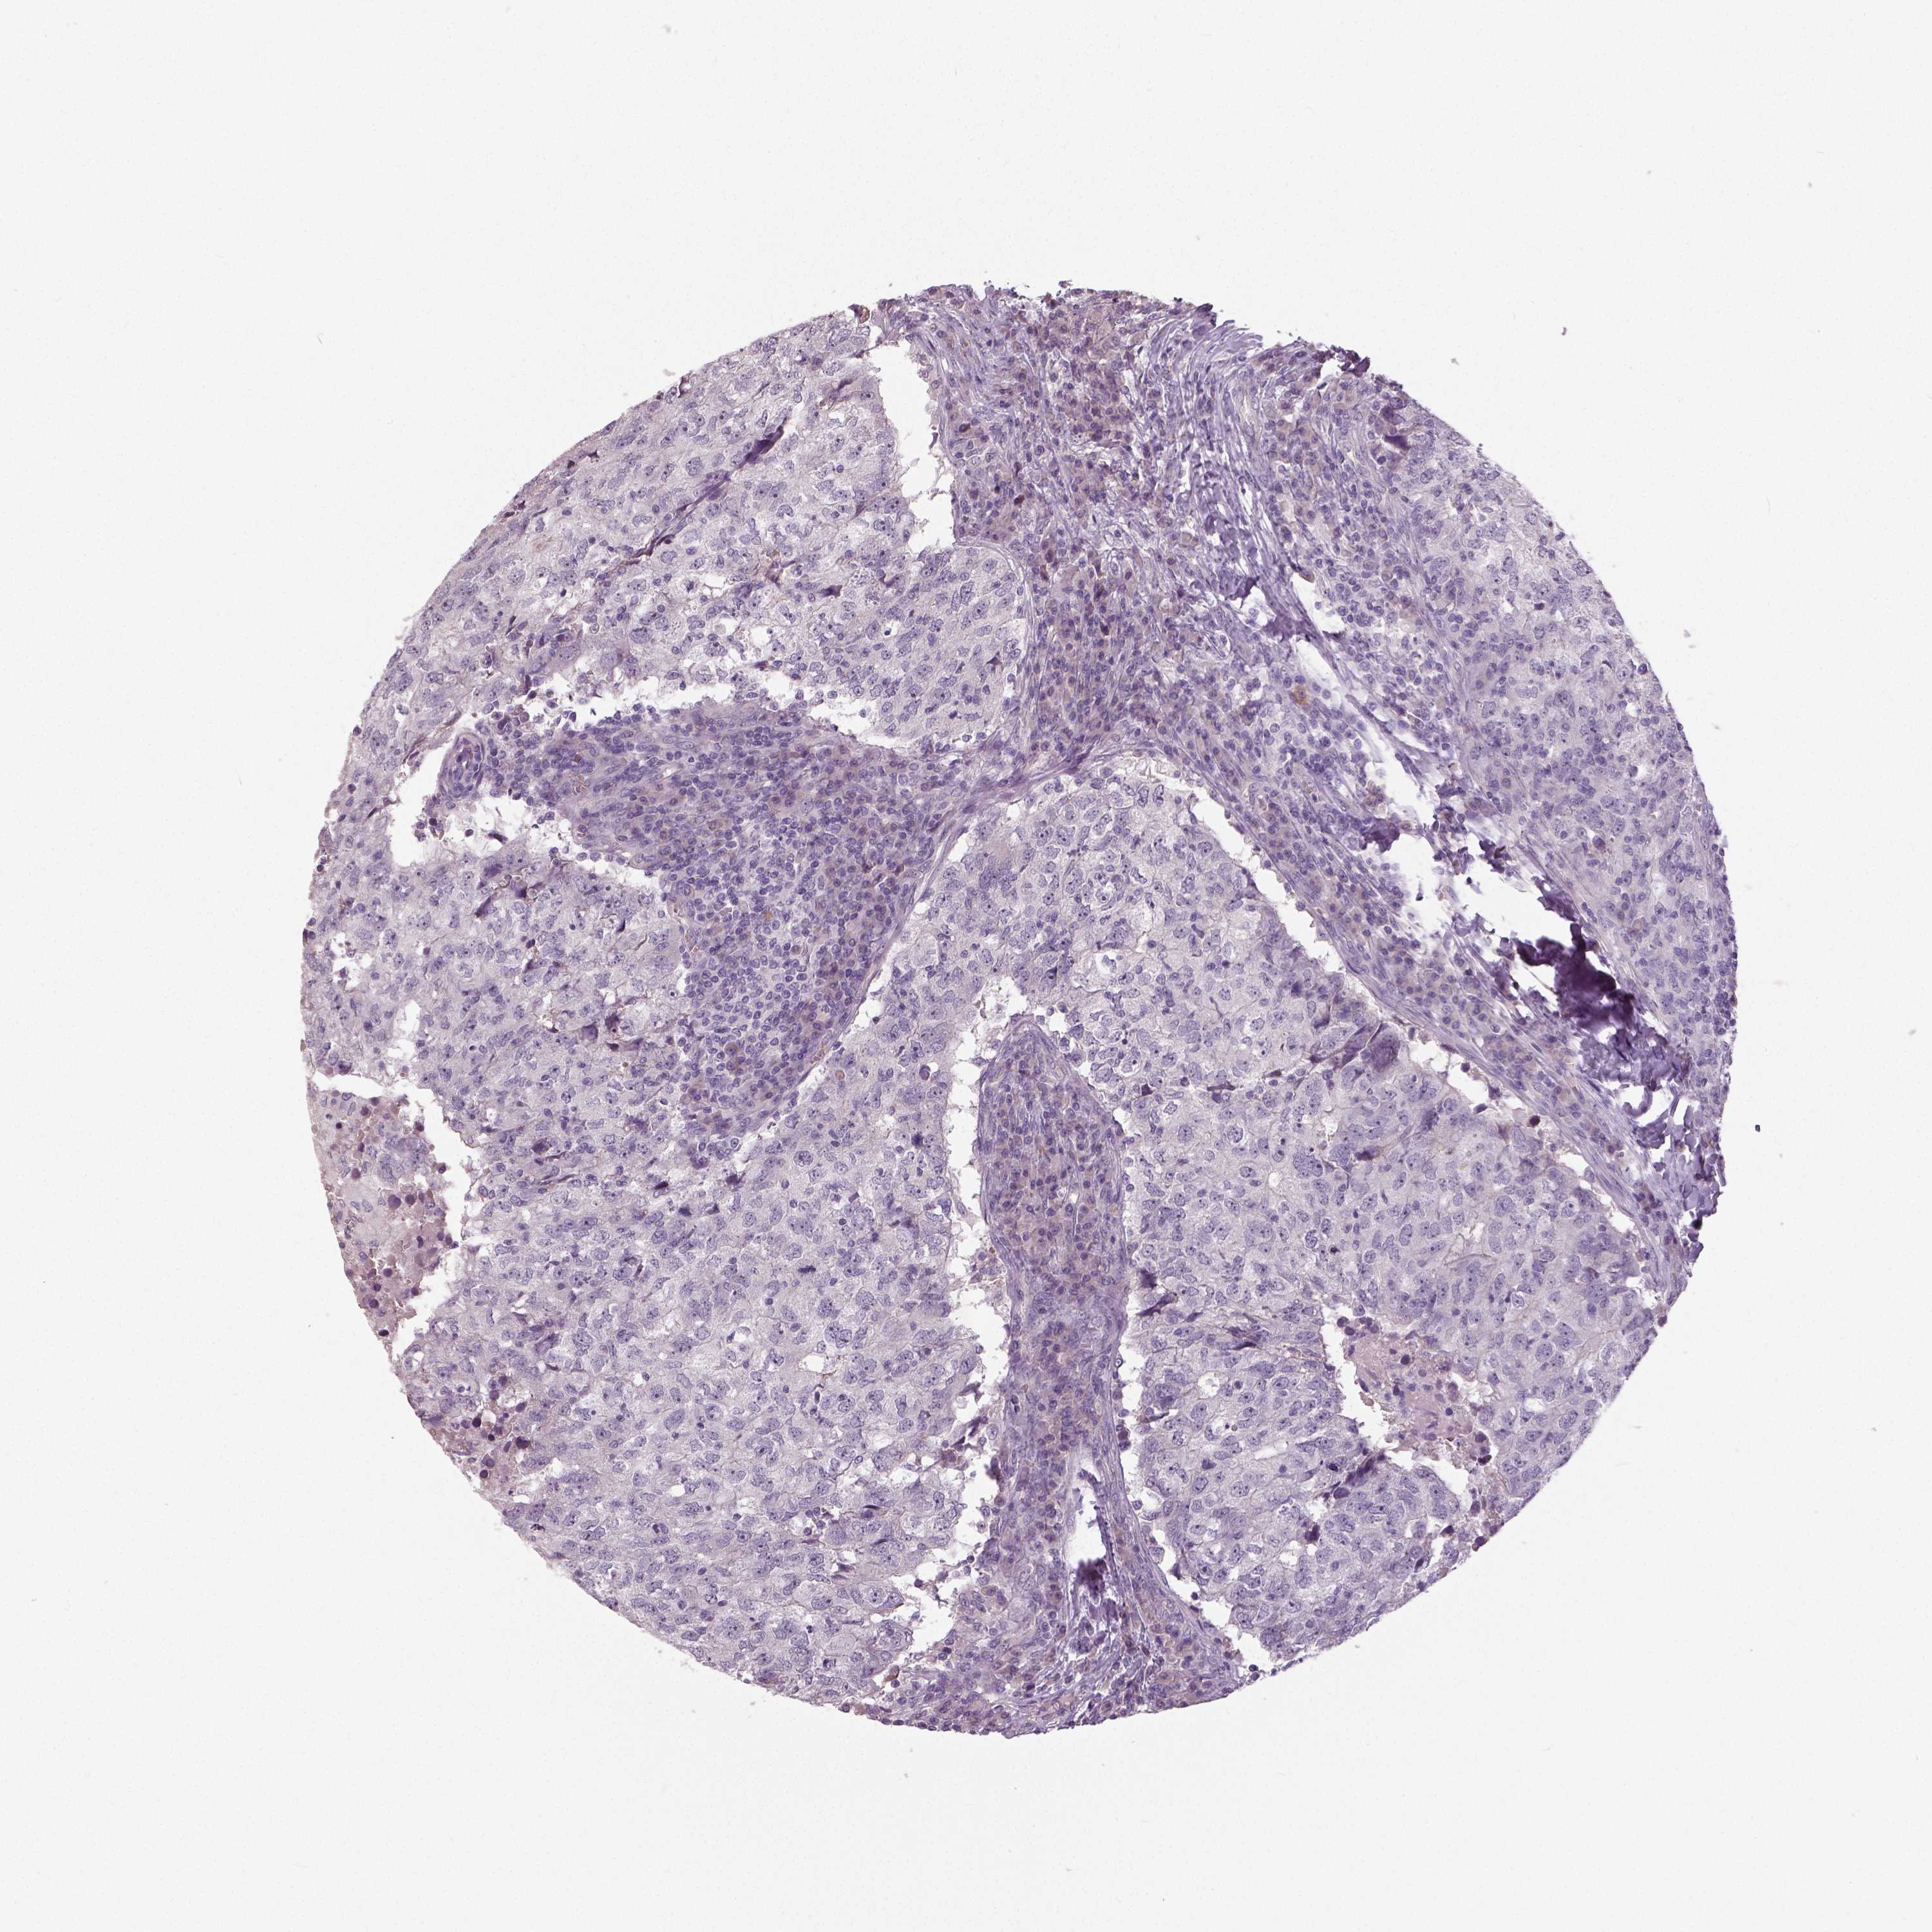

Breast cancer

Human cancer